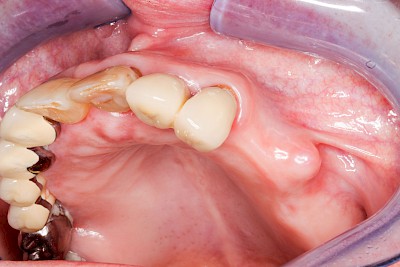

Überbeine im Bereich der Kiefer sind gar nicht so selten. Häufiger im Bereich der Seitenzähne unterhalb des Zahnfleisches, aber auch in der Mitte vom Gaumen. Überbeine haben in dem Sinne keinen Krankheitswert, müssen also nicht operativ entfernt werden, wenn diese nicht stören. Überbeine können ein Anzeichen für Knirschen und Pressen sein.

Gehen die Zähne verloren, baut häufig auch der Kieferknochen ab (Knochenschwund). Die Geschwindigkeit und das Ausmaß des Knochenschwundes ist von vielen Faktoren abhängig. Neben der genetischen Veranlagung spielen auch Überbelastungen in Folge, z. B. bei ständigem Knirschen oder Pressen, eine Rolle. Auch wenn Zahnprothesen Tag und Nacht getragen werden, kann die ständige Belastung der Schleimhäute und des Knochens den Knochenschwund beschleunigen.

In seltenen Fällen schwindet nur der Knochen, aber nicht die bedeckenden Schleimhäute. In diesen Fällen spricht man von einem sogenannten "Schlotterkamm".